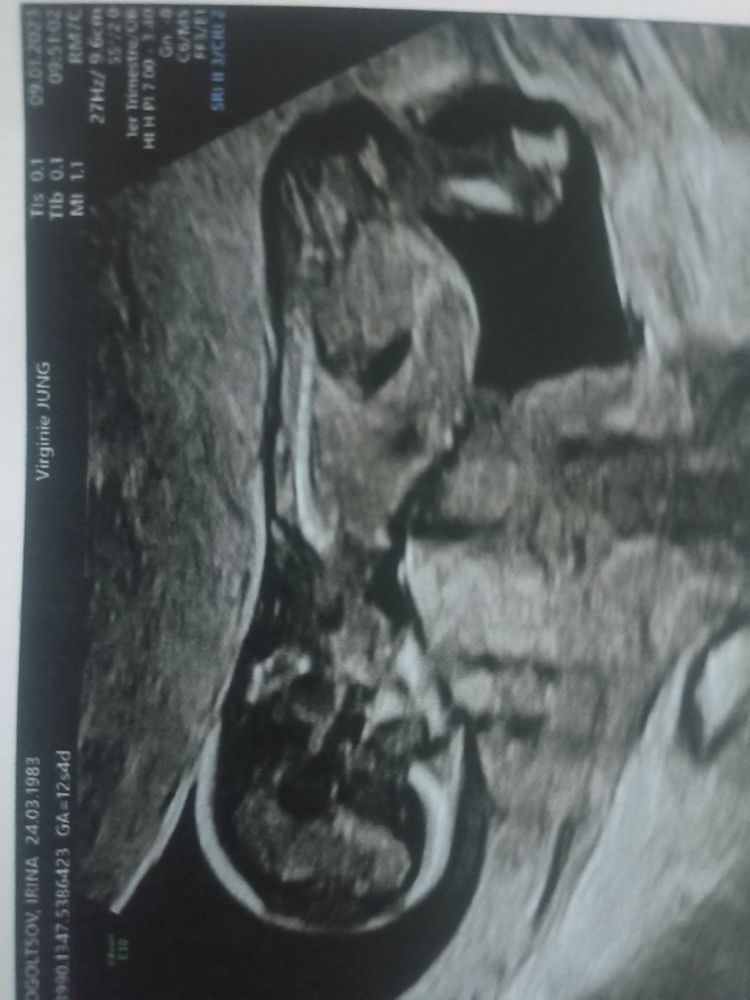

Пол ребенка не увидели, сначала спинкой, потом ножки скрещены были, но врач сказала, что догадывается кто. Следующий раз посмотрим снова.

Ну кто у нас хорошо разбирается в снимках, предположите пожалуйста, хотя я ни бугорка не нашла, ни мошонки, ни хвостика.